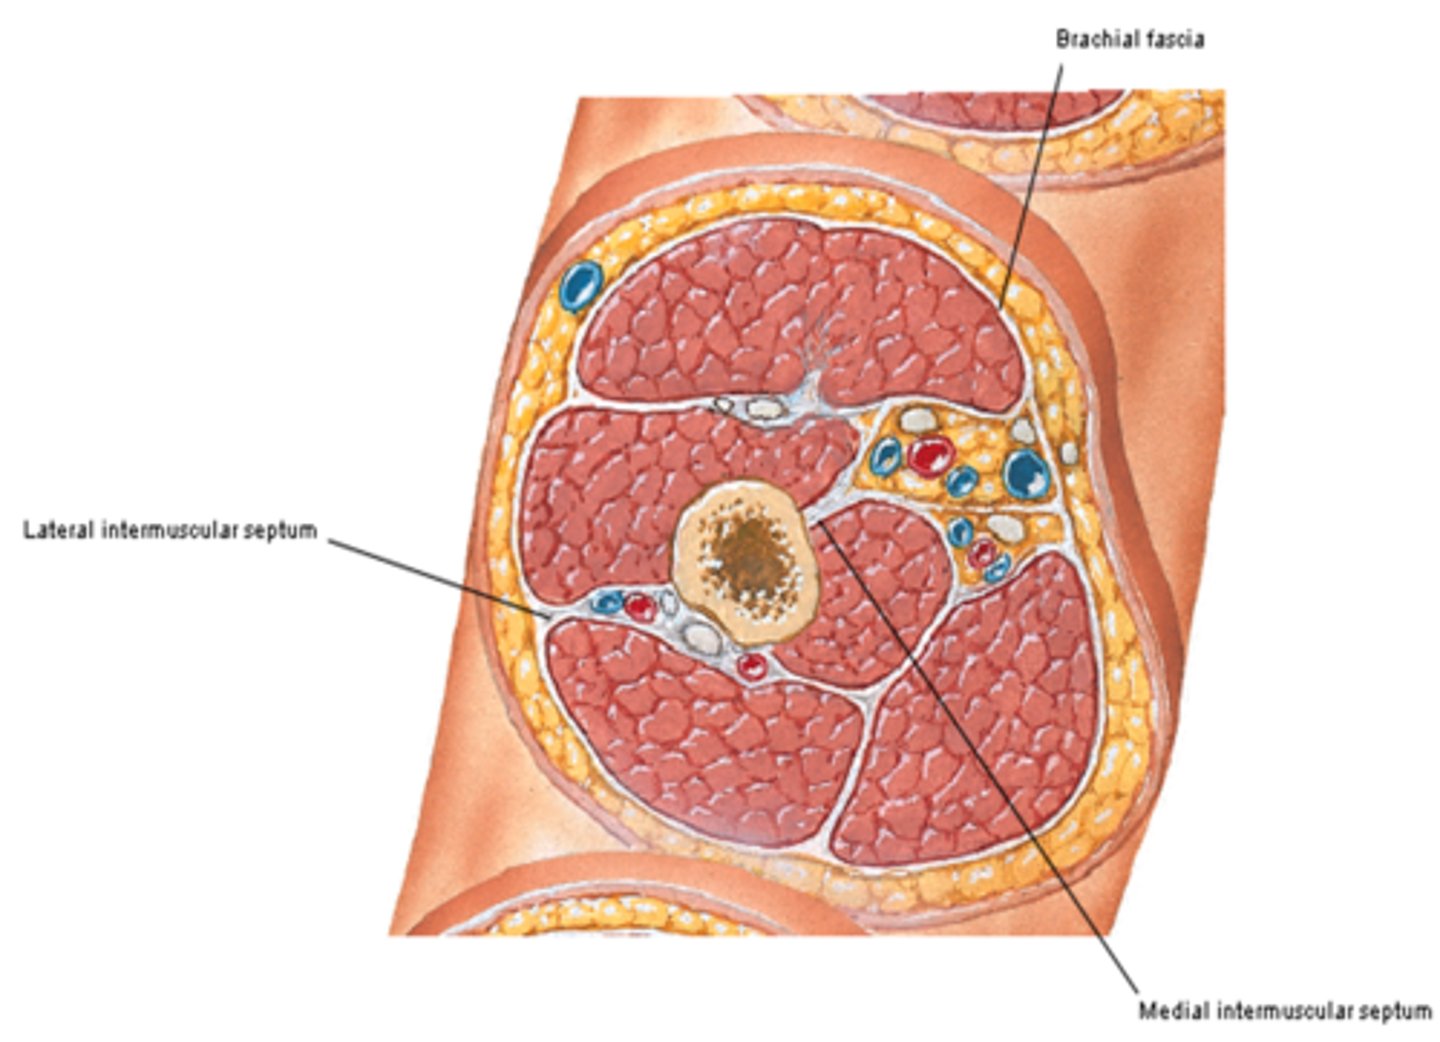

(Fascia of arm region:) Brachial fascia

sheath of deep fascia that encloses the arm like a sleeve deep to skin and superficial fascia. It is continuous superiorly with the deltoid, pectoral, axillary, and infraspinous fascias, and inferiorly with the antebrachial fascia (at the level of the elbow)

- Contains Medial & Lateral intermuscular septa

(Brachial Fascia:) Medial & Lateral intermuscular septa

extensions of brachial fascia that attach to the bone, forming fascial compartments that limit spread of infection and hemorrhage in the arm

-Anterior (flexor) fascial compartment

-Posterior (extensor) fascial compartment